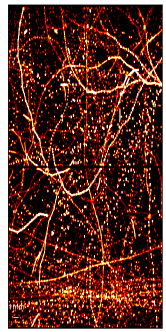

Figure 3: SR images of the test dataset, i.e., the last 100 frames of a simulation video from the challenge dataset obtained from (a) Ground Truth (b) DETR and (c) DE-DETR.

The mAP and mAR for DETR are: 80.12% and 55.17% and for DE-DETR they are: 87.60% and 63.79%. The super-resolution maps are generated using a proper Gaussian around each MB location and shown for comparison in Figure 3.